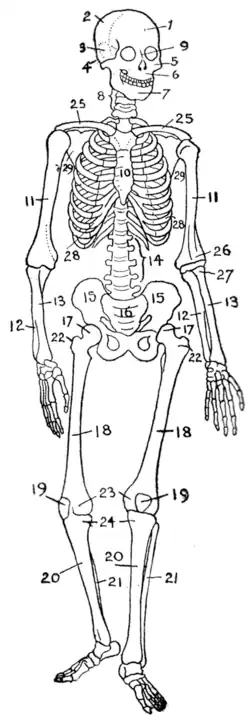

- Musculoskeletal system: muscles provide movement and a skeleton provides structural support and protection with bones, cartilage, ligaments, tendons

- List of bones of the human skeleton

- List of muscles of the human body